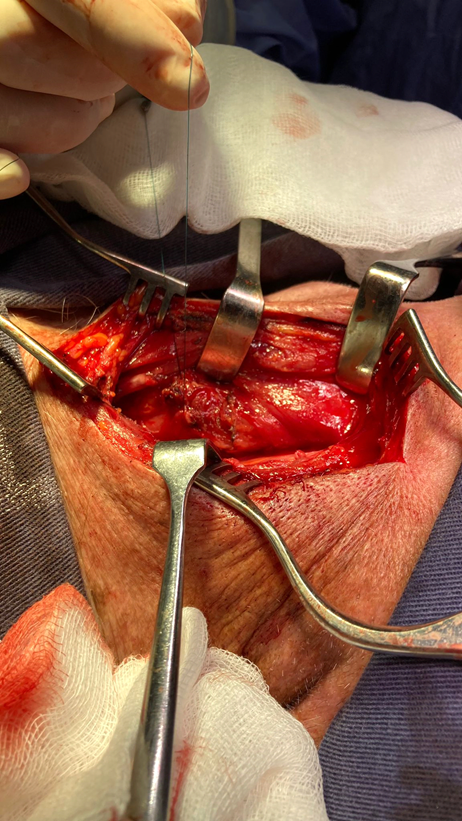

This passage of the 32 Fr tube allows to calibrate the esophagus avoiding the narrowing of the lumen, assuring a good passage of the alimentary bolus. Once calibrated, we are able to perform the diverticular section. The authors prefer the use of mechanical suture with triple row of hooks, violet or gold charge. The non-opening of the mucosa avoids contact of the esophageal lumen with the surrounding tissue, thus avoiding contamination (Figure 8 and 9).

Figure 8 Dissection of diverticulum up to the neck after esophageal calibration. Section with gold-loaded mechanical suture. Calibration of the esophageal lumen with a thick probe is a very important point of the surgery since it avoids narrowing the lumen and therefore postoperative dysphagia.

Figure 9 Diverticulum resection. This type of gold or violet load is preferred since it presents triple row of agrafes giving greater security to the procedure. The resection specimen is sent for definitive anatomopathological study.

Reinforcement stitches are made covering suture with absorbable monofilament thread polydioxanone 4-0 using the inferior fibers of the inferior constrictor of the pharynx (Figure 10). At this moment we remove the chest tube and we place a nasogastric tube also under mink up to the gastric chamber which is used as a feeding route in the postoperative period. We leave a glove sheet or suction drainage at cervical level, which is removed after the 3rd day. We perform a barium transit prior to the reestablishment of the oral route in order to evaluate the passage and rule out leakage.

Figure 10 Suture reinforcement with monofilament thread using muscle fibers of the inferior pharyngeal constrictor. At this time the chest tube is changed to a thick nasogastric tube, which will remain in the postoperative period.